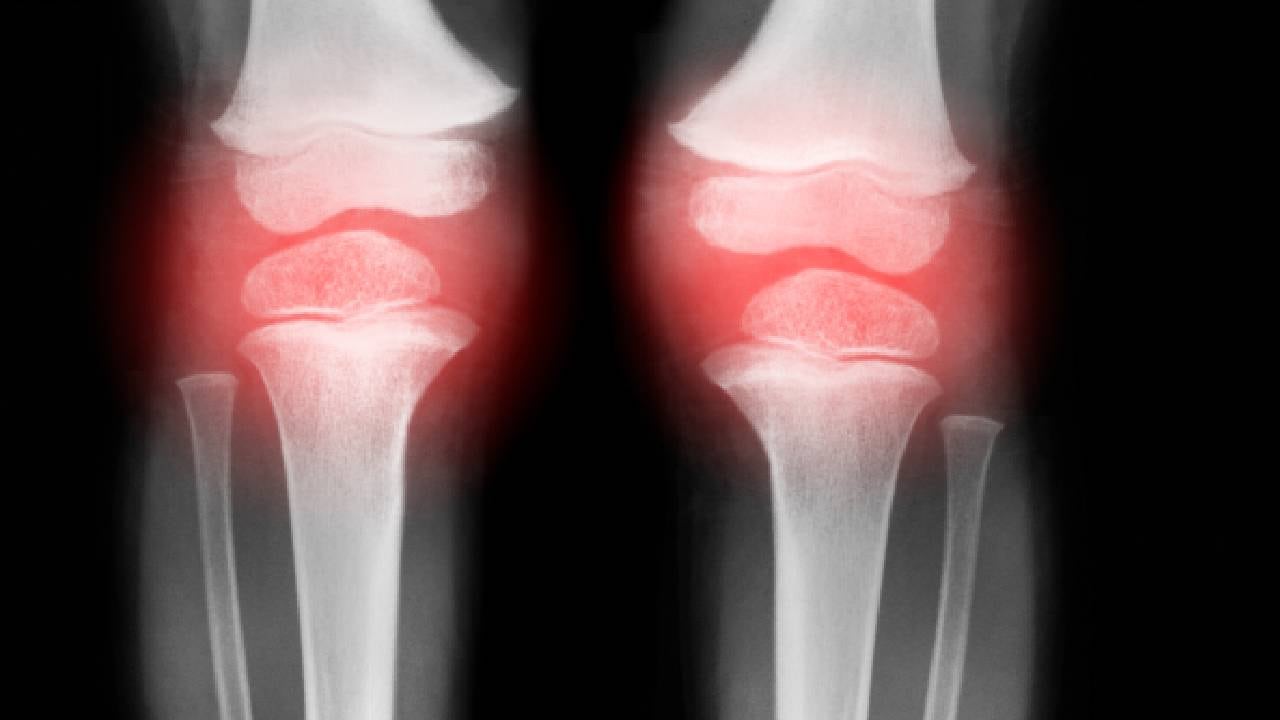

El desgaste de cartílago en la rodilla o artrosis de rodilla, es una enfermedad degenerativa, que se presenta con mayor frecuencia en personas de una edad avanzada.

No obstante, esta degeneración también se puede dar en personas jóvenes debido a las lesiones previas en la rodilla. La razón se debe a que el cartílago se desgasta gradualmente disminuyendo la protección de los huesos.

Cabe mencionar que la rodilla es una de las articulaciones del esqueleto humano en donde constantemente se desarrolla la artrosis y es porque la rodilla es una articulación “de carga”, es decir, esta debe soportar el peso del cuerpo.

Asimismo, la artrosis de rodilla, por lo general, se desarrolla lentamente y la progresión de dolor suele seguir la misma progresión, aunque también se puede dar por descompensaciones espontáneas.

- Inflamación de la articulación.

En los casos más severos de la enfermedad, se produce una disminución en los movimientos que se puede realizar con la rodilla, por ejemplo, no poder flexionar la rodilla.

Además, pueden aparecer ciertas deformidades de la articulación y alteraciones en la alineación de los huesos. Es normal que se cojee al caminar y que la rodilla se debilite.